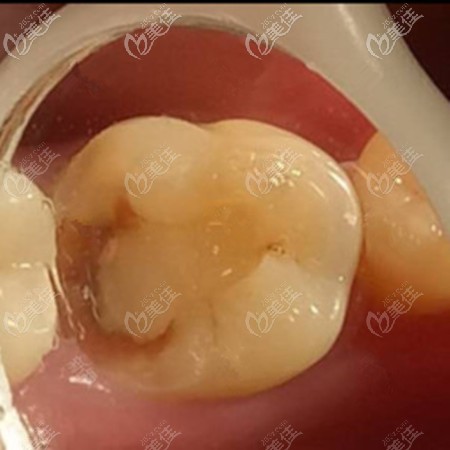

術(shù)前照片:

你可以看一下填充后的顏色尤其的逼真,主要是色澤還比較好,不會(huì)特別的呆板,一看就是假的。